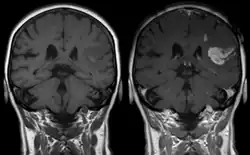

Les chélates de Gd3+ sont hydrophiles et franchissent seulement une barrière hémato-encéphalique compromise, telle que les lésions et les tumeurs.

Le gadolinium (sous forme chélatée ou libre) est retenu dans le cerveau, en particulier dans le noyau dentelé et le globus pallidus[12], dès une injection d'un agent de contraste à base de gadolinium (GBCA) (en quantité plus importante pour les linéaires)[13]. Le système glymphatique pourrait être la voie d'accès principale des GBCA au cerveau en intraveineuse[14]. Des études in vitro ont trouvé les agents linéaires (chélateurs moins stables) plus neurotoxiques que ceux macrocycliques[15],[16]. Une étude a trouvé qu'un rehaussement du signal T1 sans administration de contraste (indicateur de la présence de gadolinium) sur les IRM cérébraux d'individus ayant reçu une ou plusieurs injections d'agents linéaires et macrocycliques corrélaient significativement avec une fluence verbale moindre[17]. La confusion est une possible conséquence clinique reportée par plusieurs études[15].